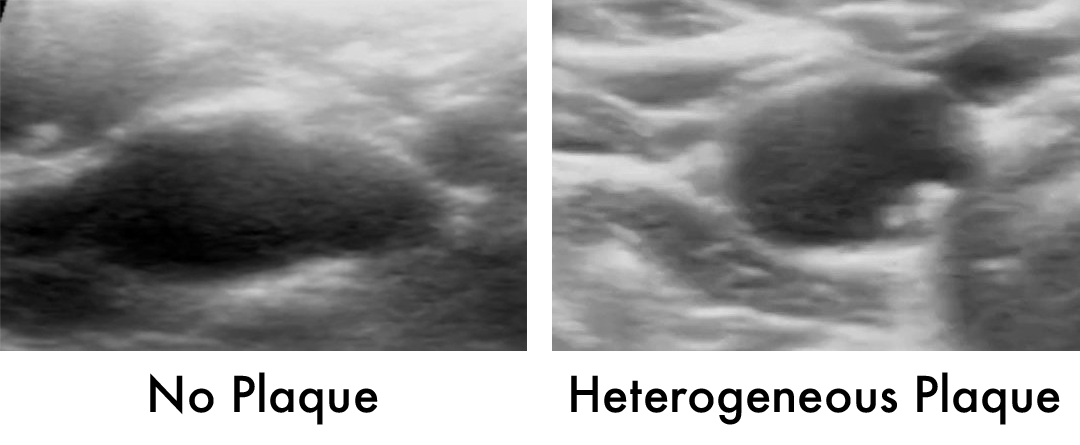

• Homogeneous plaque: This fresh, soft vulnerable plaque is like a new pimple. It is the most dangerous stage of plaque evolution because it is most likely to rupture and cause a heart attack or stroke.

• Heterogeneous plaque: This type of plaque is like a pimple that is healing. It can still rupture or erode because inflammation has not resolved. It is the most common stage of plaque seen on imaging of arteries. It is an uneven buildup of inflammatory material, fibrin, and calcium.